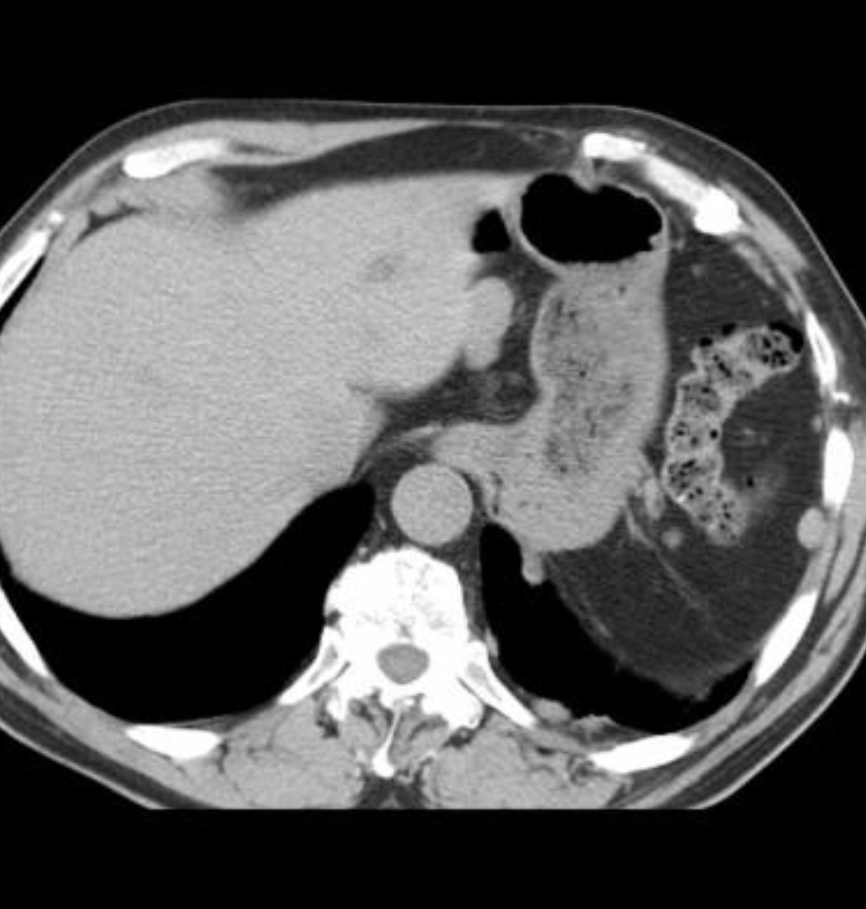

In a patient w/remote hx of blunt chest trauma and no spleen

Splenosis

autotransplantation of splenic tissue following traumatic or surgical disruption of the spleen.

Look for multiple pleural masses in the left hemithorax in a patient with a history of remote trauma.

Tc-99m sulfur colloid is often used to diagnose (uptake in splenic tissue, specifically reticuloendothelial tissue).